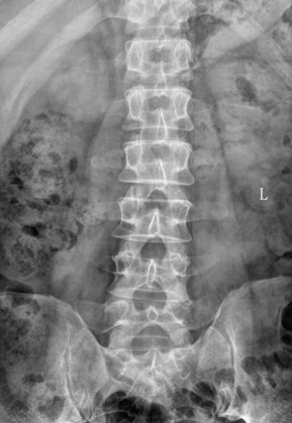

查体:扶拐跛行步态,起坐困难,脊柱轻度代偿性侧弯,腰4/5棘突及椎旁压痛、叩击痛明显,腰部活动受限。腰痛向左侧大腿后侧、小腿后外侧放射致足背,足背麻木感,较对侧感觉减退,踇趾背伸肌力4级,直推抬高实验30°阳性。术前影像:X线见:腰4/5椎间隙变窄,腰椎前凸变小,未见明显腰椎不稳定。

术前CT见:腰4/5椎间盘巨大凸出向后下方,左侧旁中央及侧隐窝狭窄明显,伴腰4、5椎体后缘钙化。

腰椎MRI见:腰4/5椎间盘变性,椎间盘巨大突出,硬膜囊受压明显,左侧椎间孔明显狭窄,左侧神经根受压明显。